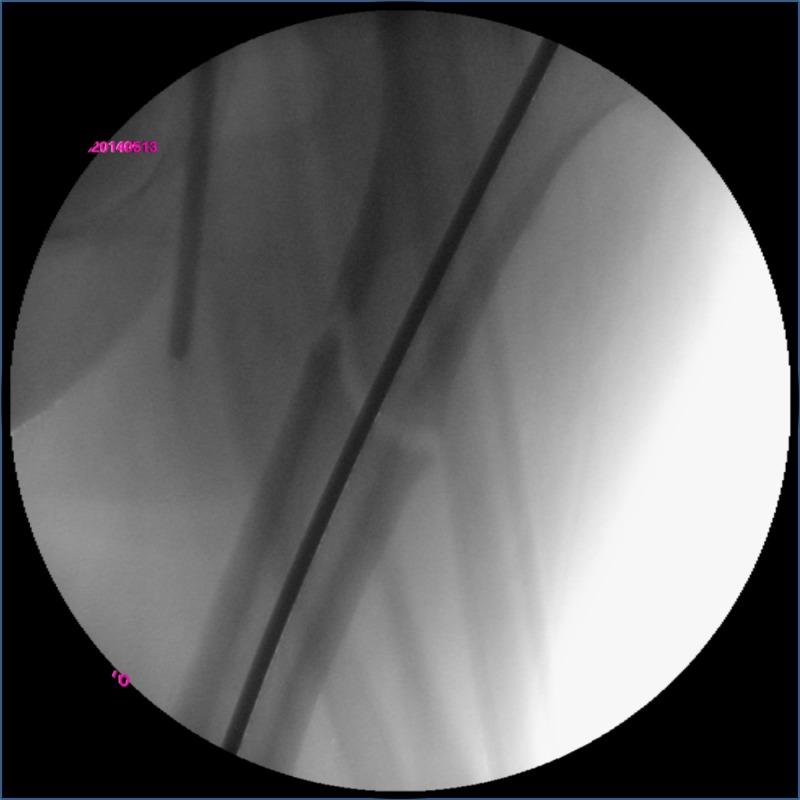

A subtrochanteric fracture of the femur accompanying pre-existing osteoarthritis of the ipsilateral hip is rare. A deformity of the hip joint complicates the insertion of the intramedullary nail and varus malreduction is anticipated when surgery is performed on a fracture table with a perineal post. We report a successful case of intramedullary fixation performed in the lateral decubitus position and discuss the importance of avoiding varus and the superiority of the lateral position in surgery.